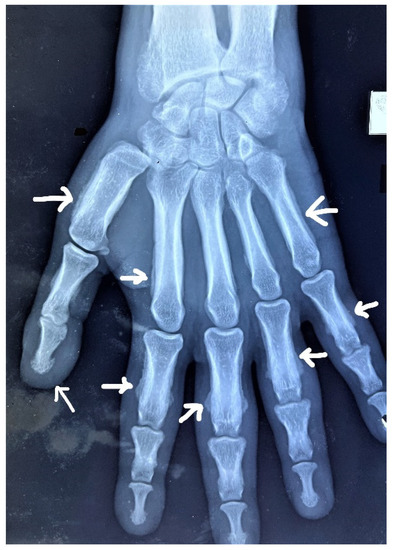

2. Case Report